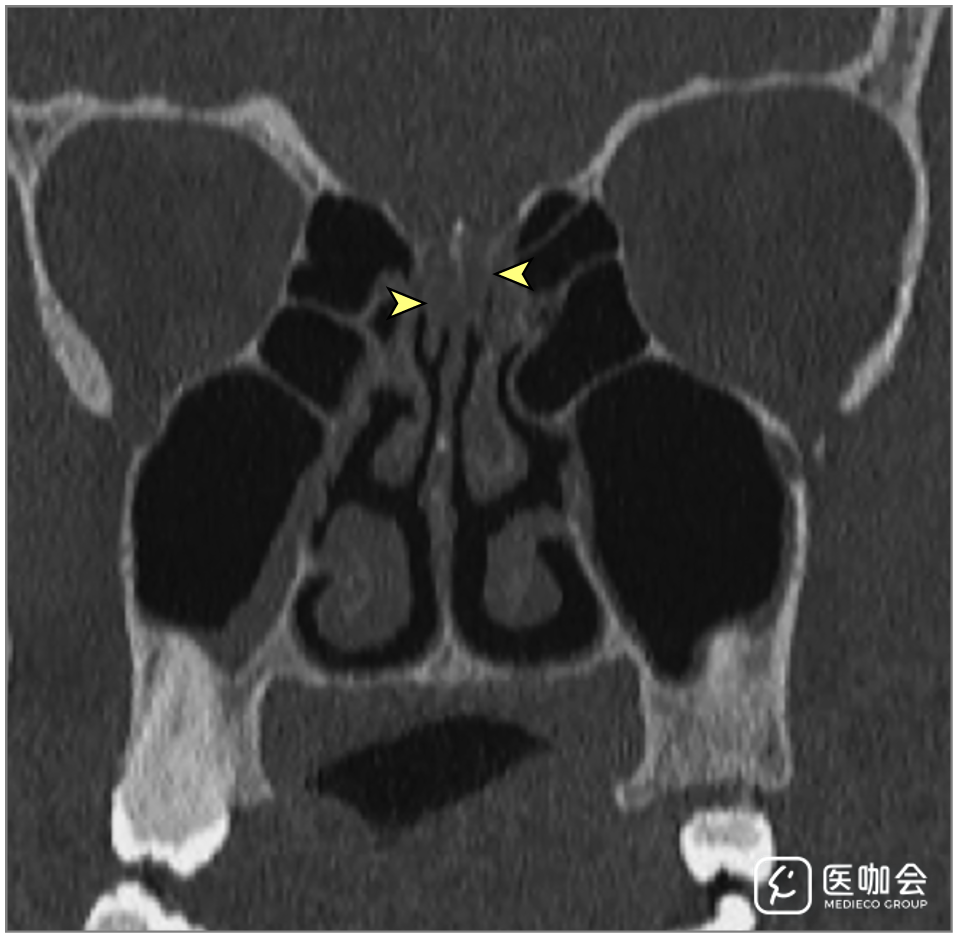

患者接受了鼻腔CT检查(图1),显示双侧嗅裂区的炎性阻塞,经鼻腔MRI再次确认了这一结果(图2)。患者的嗅球和嗅神经束未见异常。由于她的丈夫被怀疑感染了SARS-CoV-2,因此该患者也接受了SARS-CoV-2的RT-PCR,结果呈阳性。

图1